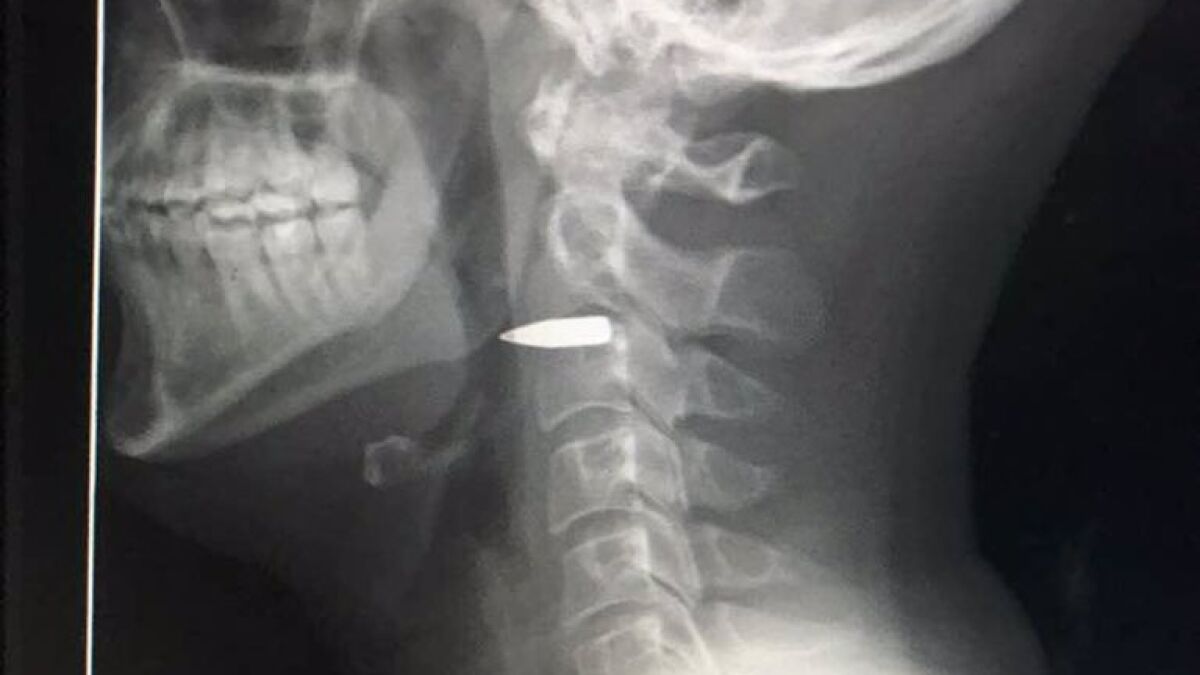

Fue trasladado de urgencia al hospital donde le hicieron una radiografía en la que se ve la bala alojada en su cuello.

"Gracias a todos-estoy bien. La bala está aún en mi cuello, pero no impactó en nada importante", escribió el reportero en su cuenta de Twitter.